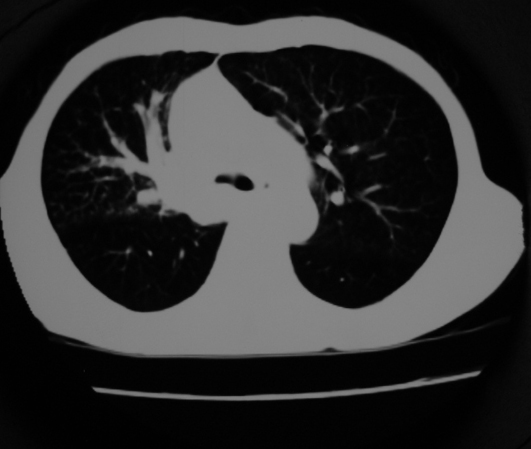

以下是引用同在2007-1-27 14:13:00的发言:[br]支持右侧中央型肺癌伴阻塞性病变.

以下是引用zjzjr在2007-1-27 16:56:00的发言:[br]支持右肺中心型肺癌伴阻塞性肺炎.